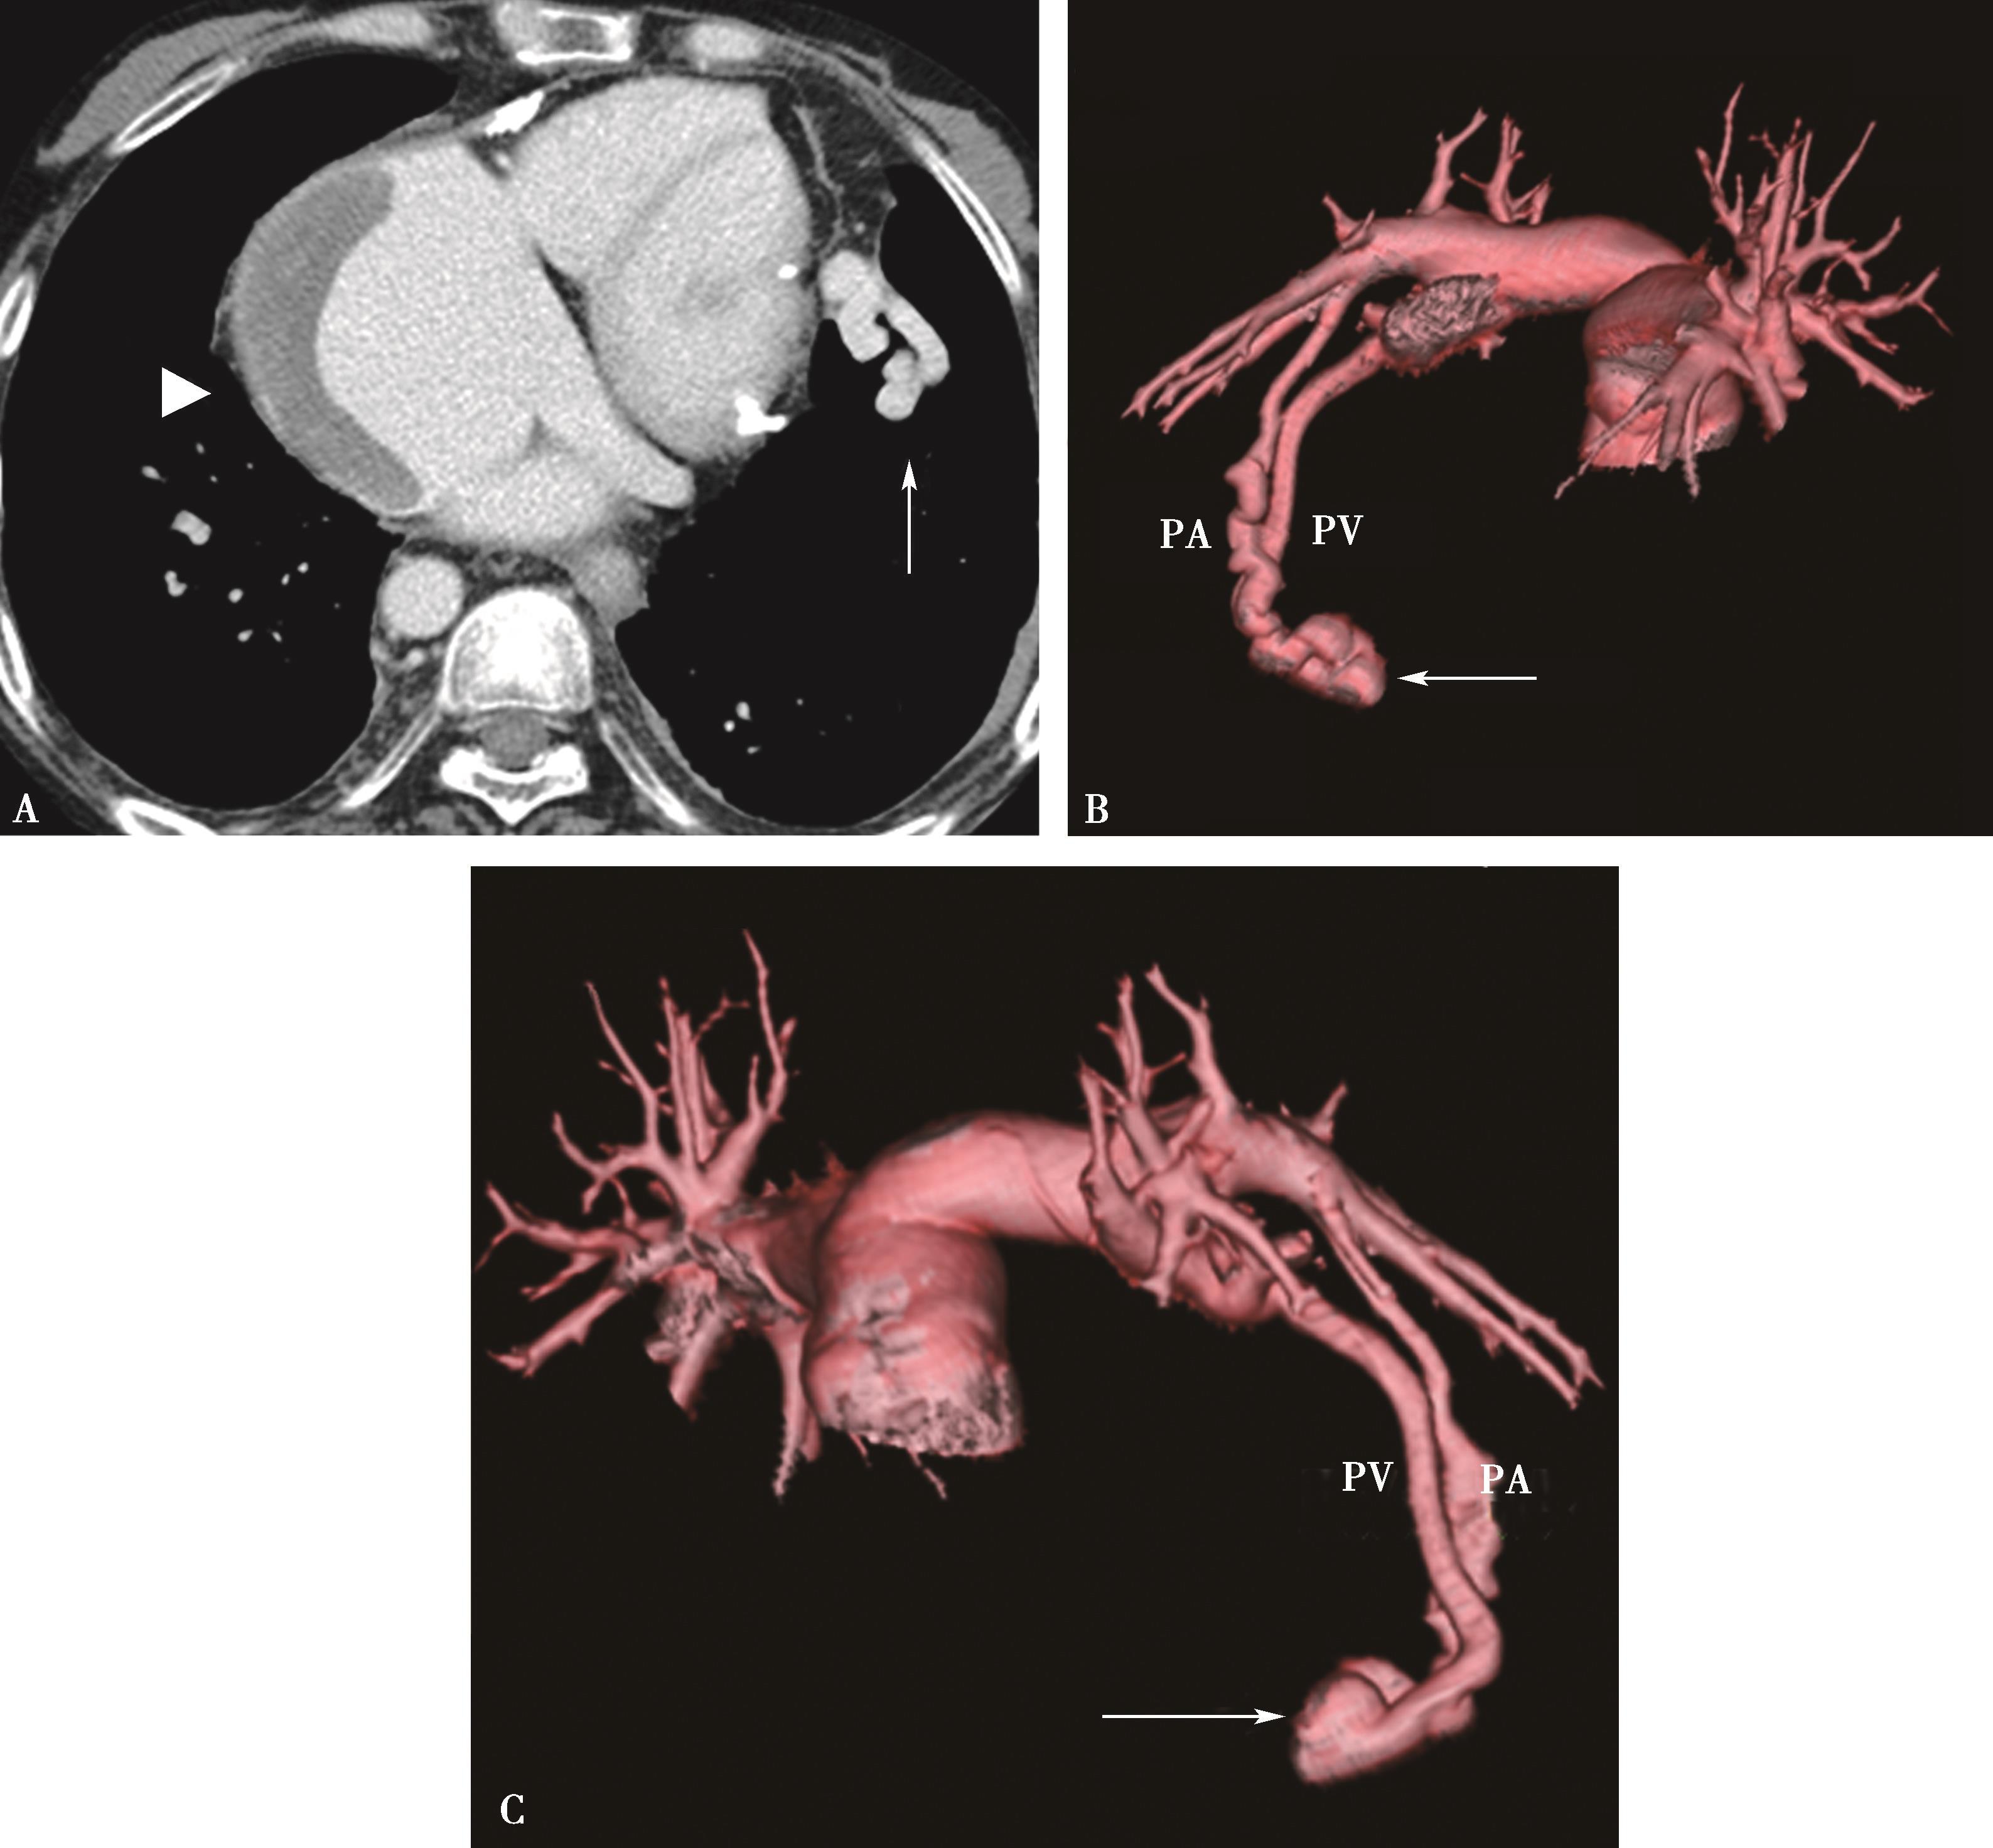

1)主肺动脉干或/和左右肺动脉干梭形瘤样扩张,腔内不同程度附壁血栓(图8-5-4)。

横断图像。A~C.主肺动脉、瘤样扩张,左右肺动脉瘤样扩张,不规则附壁血栓(↑);D~F.三维重建主肺动脉及左右肺动脉瘤样扩张,红色为附壁血栓(↑),波及肺叶分支;CT诊断:肺动脉瘤累及主肺动脉、左右肺动脉及叶分支,附壁血栓形成,病变性质考虑为白塞病

2)肺动脉叶段分支瘤样扩张,真性或假性动脉瘤形成,腔内不同程度附壁血栓(图8-5-5)。

图8-5-5 男,28岁,反复口腔及生殖器溃疡5年,白塞病,肺动脉瘤

A.胸部X线片,示左右肺动脉瘤(↑);B.横断图像,左、右下肺动脉动脉瘤形成,附壁血栓形成(↑);C.多层重组(冠状位)示右下肺动脉动脉瘤合并附壁血栓(↑);D.多层重组(左前斜位)示左下肺动脉瘤合并附壁血栓形成(↑)。CT诊断:左右肺动脉瘤,附壁血栓形成,病变性质白塞病